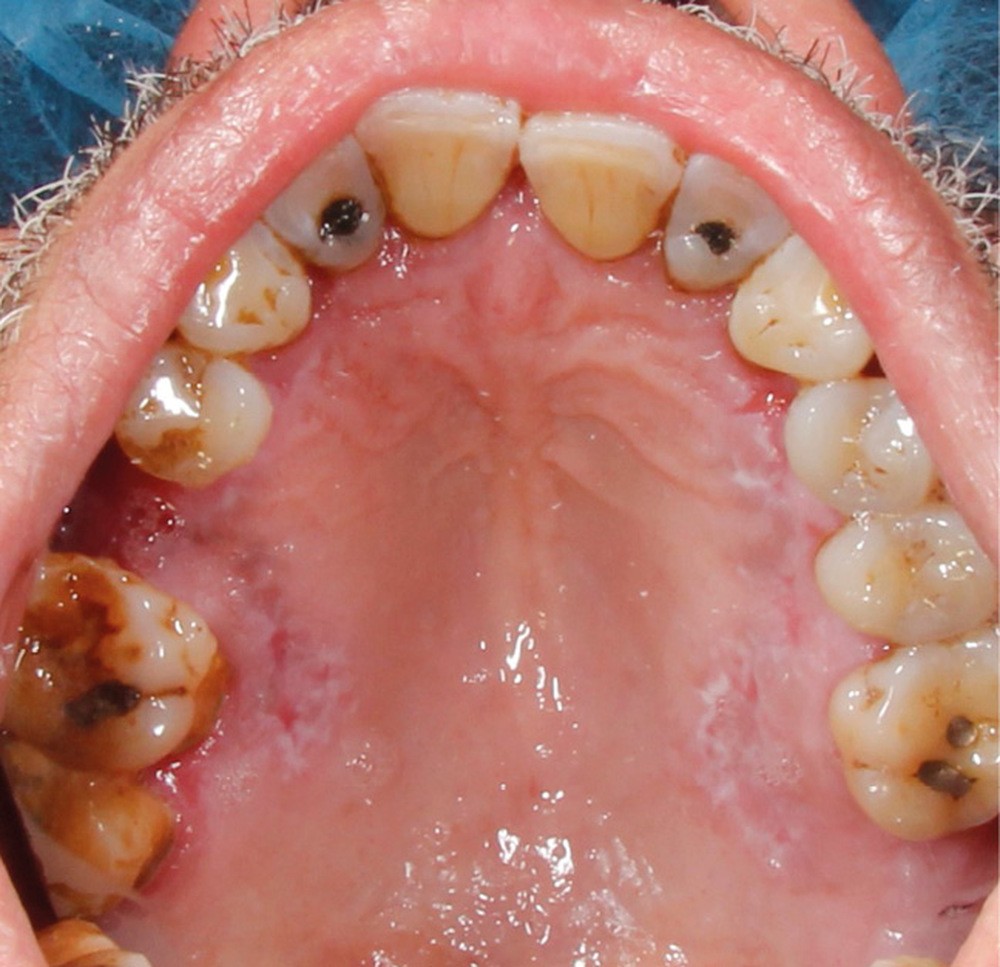

À l’interrogatoire, le patient affirme qu’il a des difficultés à maintenir une hygiène bucco-dentaire satisfaisante du fait des douleurs, et n’a pas pu consulter son chirurgien-dentiste pour son détartrage annuel en raison de la crise sanitaire en cours. L’examen clinique révèle une parodontite chronique (stade 3) généralisée et des lésions jugales (fig. 1 et 2), labiales (fig. 3) et gingivales (fig. 4) érythémateuses et kératosiques. Les lésions kératosiques jugales sont de type réticulé (fig. 1 et 2) ; les lésions kératosiques labiales sont associées à de petites érosions (fig. 3) ; les lésions palatines à des ulcérations (fig. 5). La langue présente une lésion blanche en « tache de bougie » (fig. 6) ; la muqueuse du plancher buccale est saine (fig. 7). Le signe de la pince est négatif. Le patient n’est pas porteur de prothèse dentaire malgré un édentement de moyenne étendue. Aucune lésion cutanée ou génitale n’est rapportée par le patient.

Le diagnostic le plus probable est le lichen plan (LP). On note, au niveau jugal, une kératinisation en réseau marquée par les stries de Wickman. Un phénomène de Koebner (exacerbation…